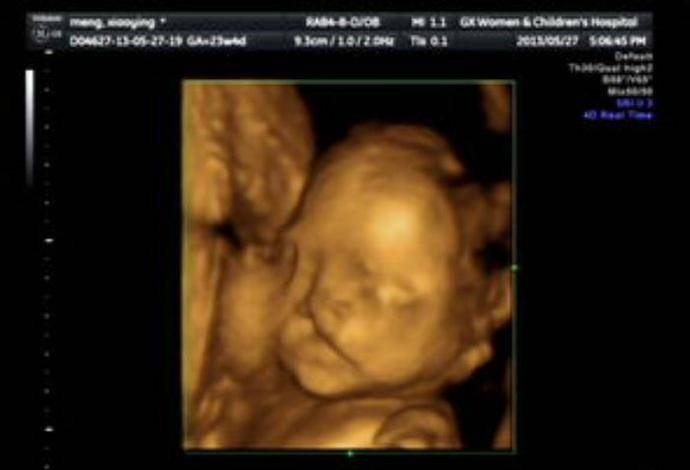

懷孕6個月!23歲孕媽照超音波「寶寶一直在笑」醫生皺眉勸:「孩子不能留」

相信每個媽媽懷孕時,最期待的就是產檢照超音波了吧!這個偉大的科技發明,除了可以讓準父母提前知道寶寶的性別,同時也能趁機跟他打招呼,看著孩子在肚子裡翻身,有些媽媽甚至會感動得哭出來。而過去就有一位來自中國大陸的年輕女子,到醫院做產檢時,發現螢幕中的寶寶正不斷朝她微笑、做鬼臉,因此高興的不得了,但是當醫生看完後,卻露出了凝重的表情,嚴肅地告訴她:「孩子不能留!」

然而,站在一旁的醫生看完後,卻皺起眉頭,露出十分擔憂的表情,嘆了一口氣對準爸媽,「還是把孩子流掉吧!」他進一步解釋,「其實孩子看起來在笑,是因為有很嚴重的唇裂,從嘴巴一直裂到了耳朵,而以目前的醫學技術,根本就無法透過手術修復如此大的缺陷,所以還是別留了,生下來對他也是一種折磨。」